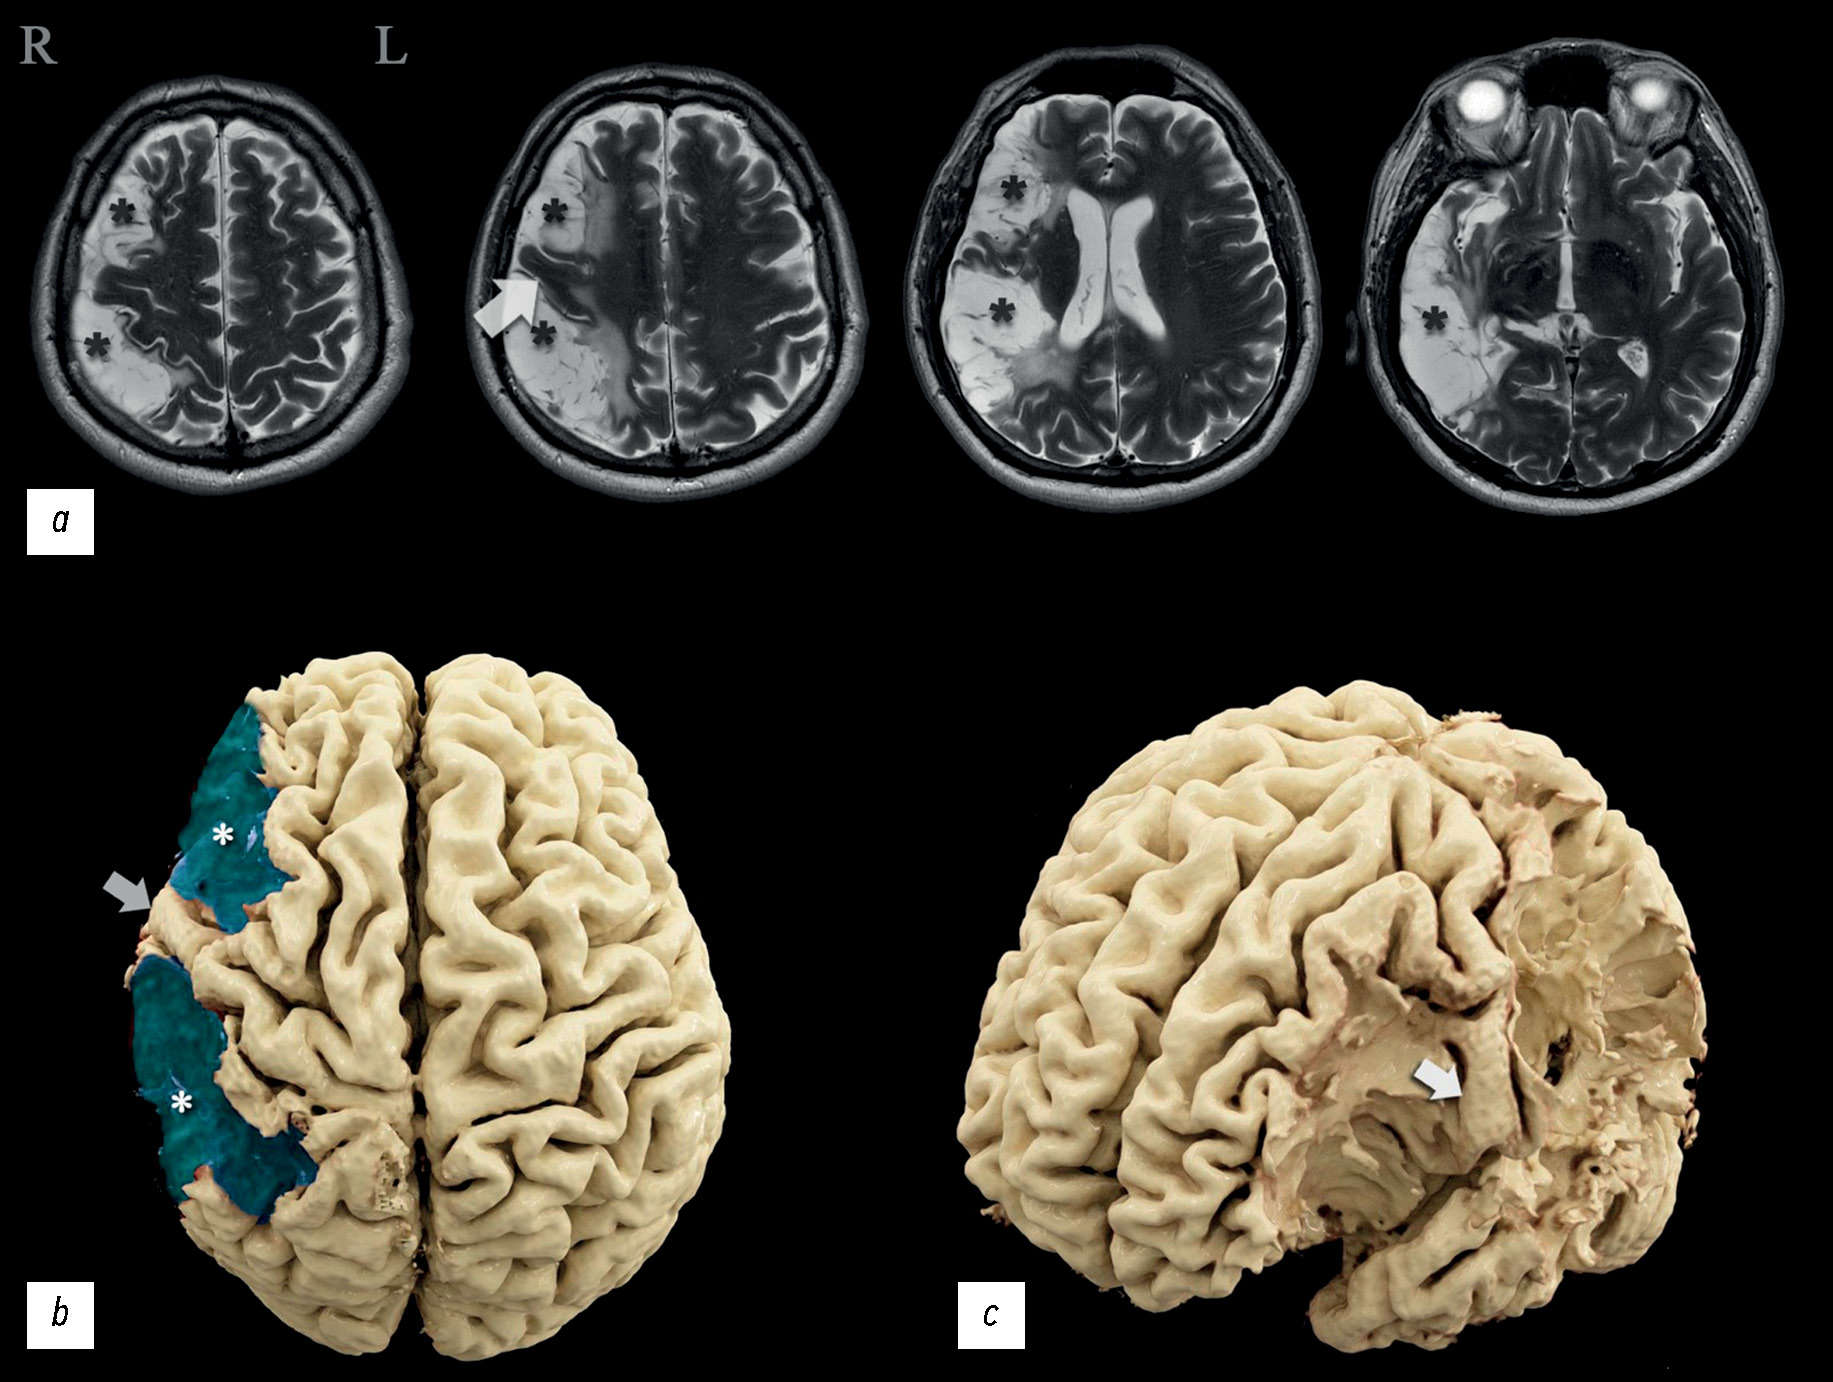

A case report of a mild neurologic deficit with extensive poststroke damage to the subdominant brain hemisphere: analysis of data obtained from magnetic resonance tractography, functional magnetic resonance imaging, and electroencephalography

The severity of damage to different brain areas, including the cortex, can vary significantly in the associated neurologic deficit and reduction in the quality of life, often regardless of the lesion volume. The localization of the abnormalities plays a large part. Lesions of the dominant and subdominant hemispheres can differ greatly in both clinical features and effects on the patient’s quality of life. In this case report, a patient admitted for rehabilitation after two ischemic strokes underwent neurological and neuropsychological examination, complex instrumental diagnostics using electroencephalography, magnetic resonance imaging, computed tomography perfusion, magnetic resonance tractography, and functional magnetic resonance imaging. The patient had minimal left-sided hemiparesis, impaired regulation of voluntary activity, mild decrease in neurodynamic indicators, mildly impaired concentration, and a critical view of his condition. Neuroimaging findings demonstrated extensive postinfarction damage to the right subdominant hemisphere of the brain in the middle cerebral artery circulation. A nonconformity between the brain damage volume and the severity of its clinical signs was observed. Based on functional examination data, the dominant hemisphere was determined, and restructuring the functional centers was suggested. This clinical case was compared with similar ones, and their relationship with the data was analyzed. Information that expands the knowledge of the topography of the altered zones involved in motor and speech functions and the ability to perform arithmetic counting was obtained.